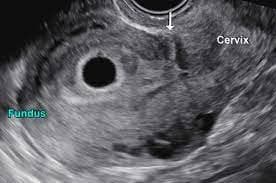

Modified curettage technique improves cesarean scar pregnancy outcomes

A study compared classical & modified ultrasound-assisted suction curettage techniques for cesarean scar pregnancy. The modified approach resulted in less postoperative hemoglobin decrease (1.01 g/dl vs. 1.39 g/dl) & lower treatment failure. Factors influencing success included myometrial thickness & gestational diameter. Results support the effectiveness of guided suction curettage, especially when detaching the gestational sac prior to suction.